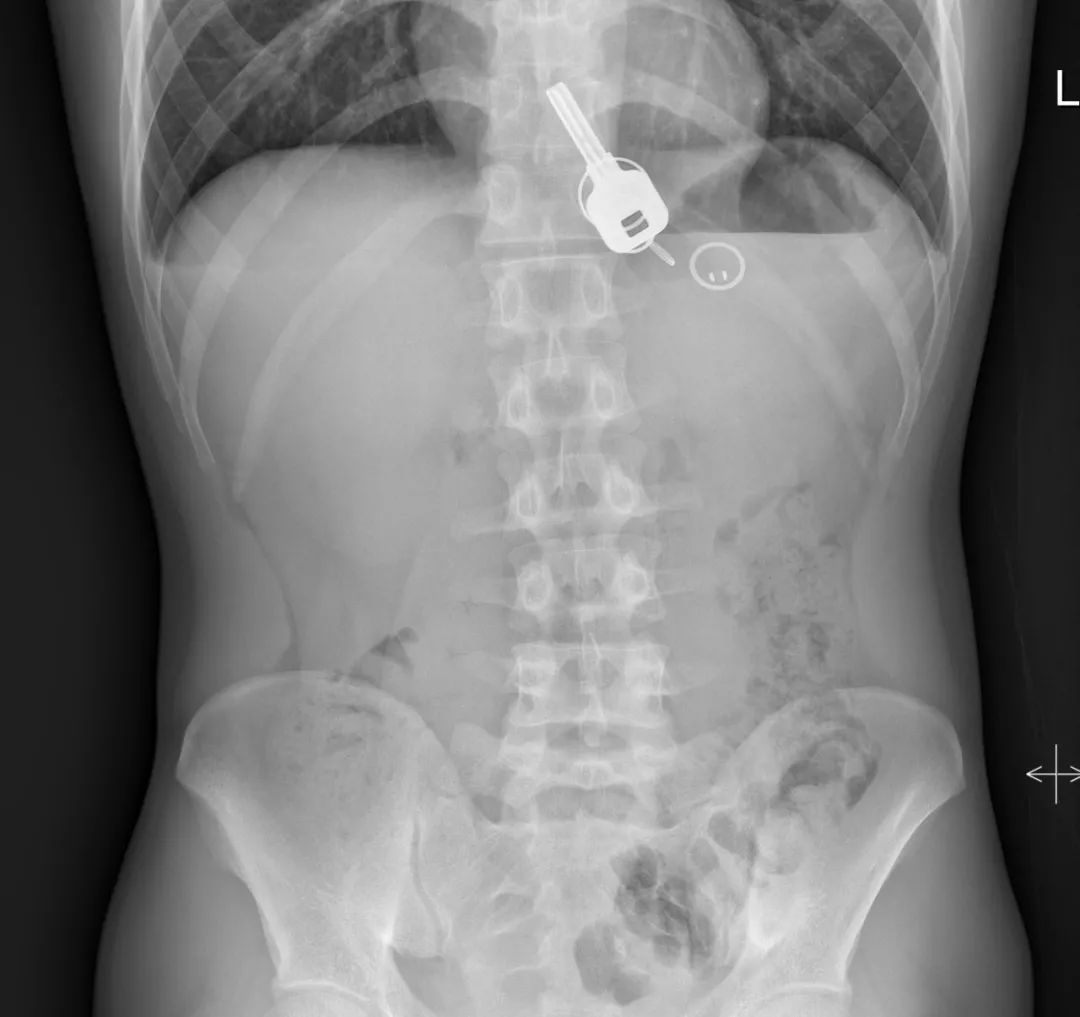

直到早上酒醒了,胸口很痛,忍不住来医院检查。结果,一拍X光,一把铁钥匙、2个钥匙扣、1个门禁牌清楚显示在肚子胃区的位置上。